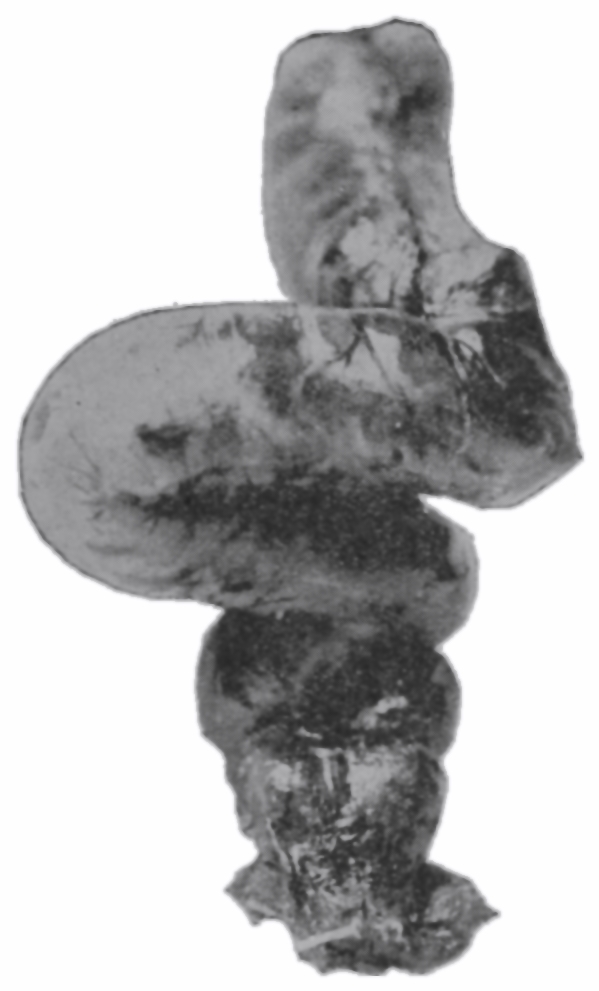

The photographic reproductions here published are documentary evidence of the existence of the obstructions under discussion. The sketch, Fig. 33, which was drawn from the valve while under the microscopic lens, exhibits the character of these obstructions and proves it that of a typic anatomic valve, and the absence of permanent bands of any other character in this organ is evidence that the semilunar valves and the so-called plica transversalis recti, Falten des Rectums, sphincter ani tertius, superior sphincter, and detrusor fecium muscles are one and the same thing and this thing is essentially a valve. It is most prominent when the gut is most distended.

The rectum may present to the eye of the imaginative observer the appearance of a chain of urinary bladders, communicating one with another by means of irregularly elliptic openings set at varying axes, and bounded by the nonparallel borders of the rectal valves. In the normal rectum the air-pressure smooths the mucous membrane evenly over the entire surface of the gut, as may be observed in the photographic illustrations. The normal mucous membrane of the so-called ampulla appears at first wet and of a shining bluish gray. As it dries, under the influence of gravitation the blue venous tint fades out of the gray and the wall assumes a pink tint.[39] Presently it acquires the appearance of parchment, and sometimes it appears painted at rare intervals with ramifying little arteries which may be crowded and overlapped by the larger companion veins; the latter are less arborescent and more suddenly dive and disappear in the bowel-wall. In time, over all there comes a sheen and the vascular pictures may fade away. These phenomena appear exactly as described only in the healthy rectum. In the diseased organ the color varies much.